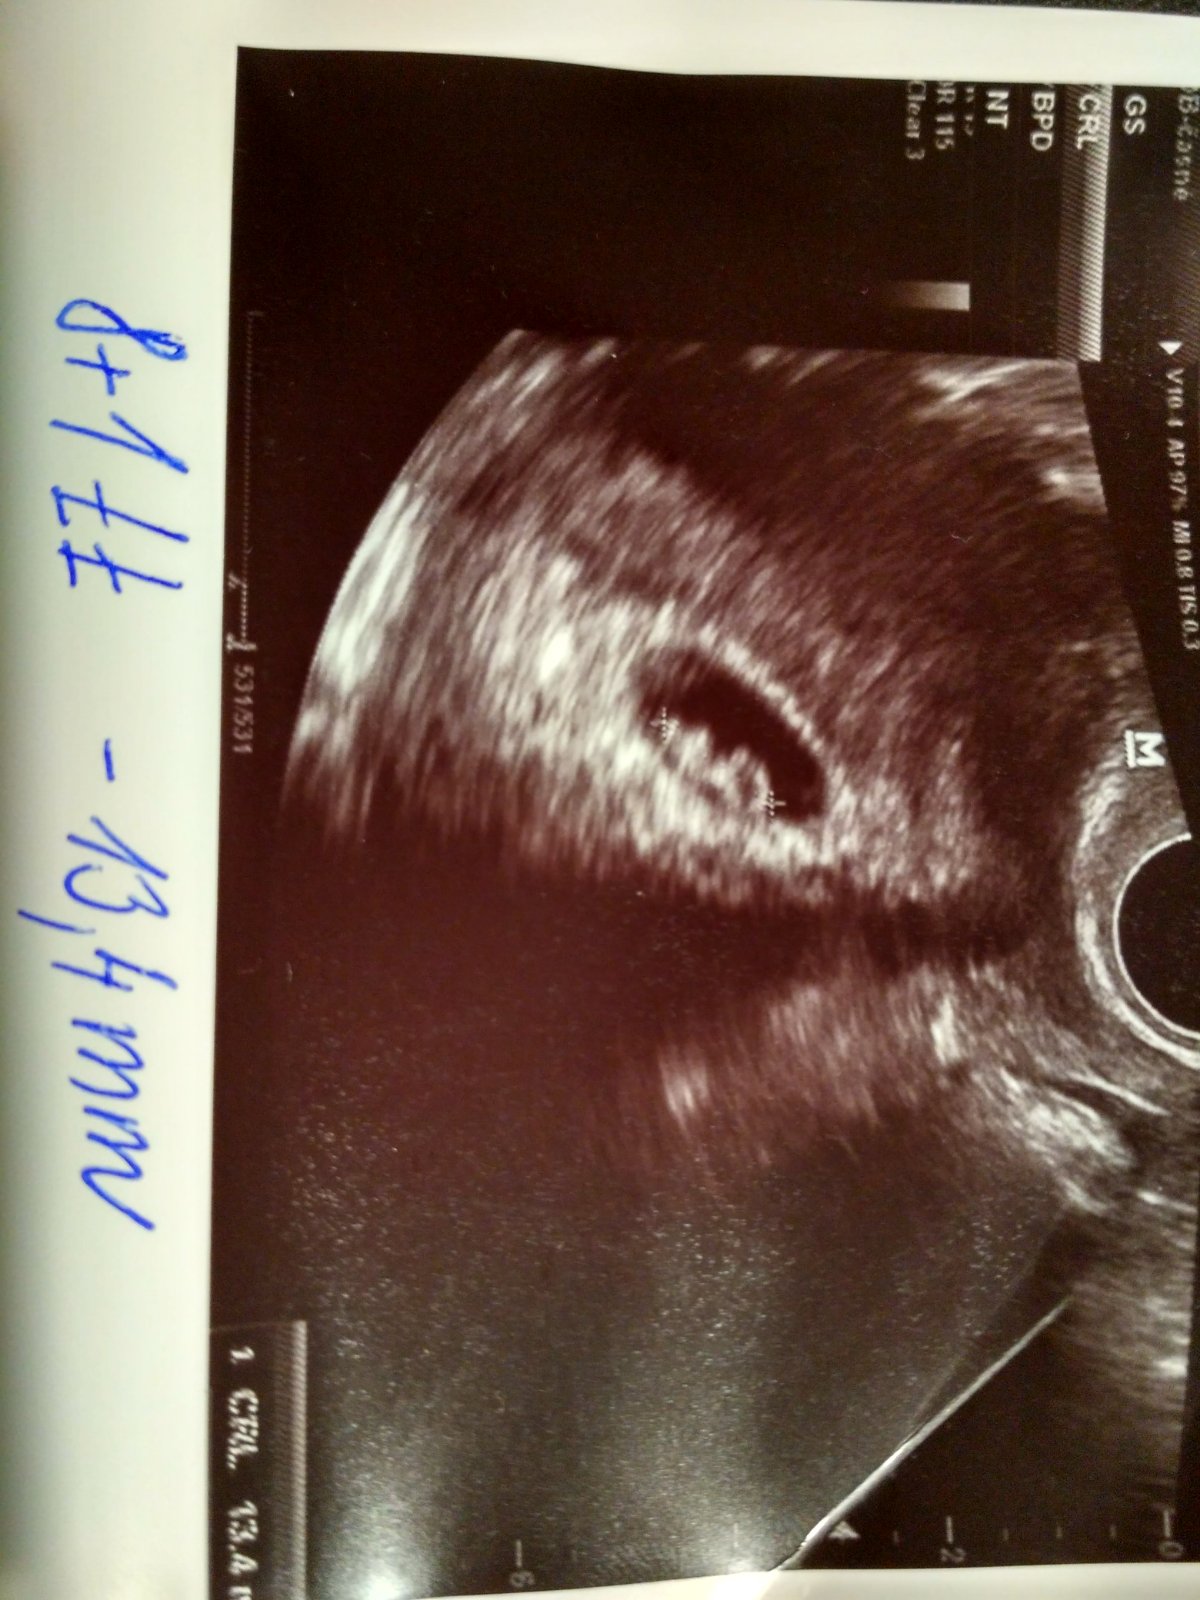

@petula.bir no krasny graf....krasny vitezny graf...moc Ti gratuluji a az budes mit fotecku fazolky,tak se nam tady pochlub....parada👍👍👍👍💕💕💕💕